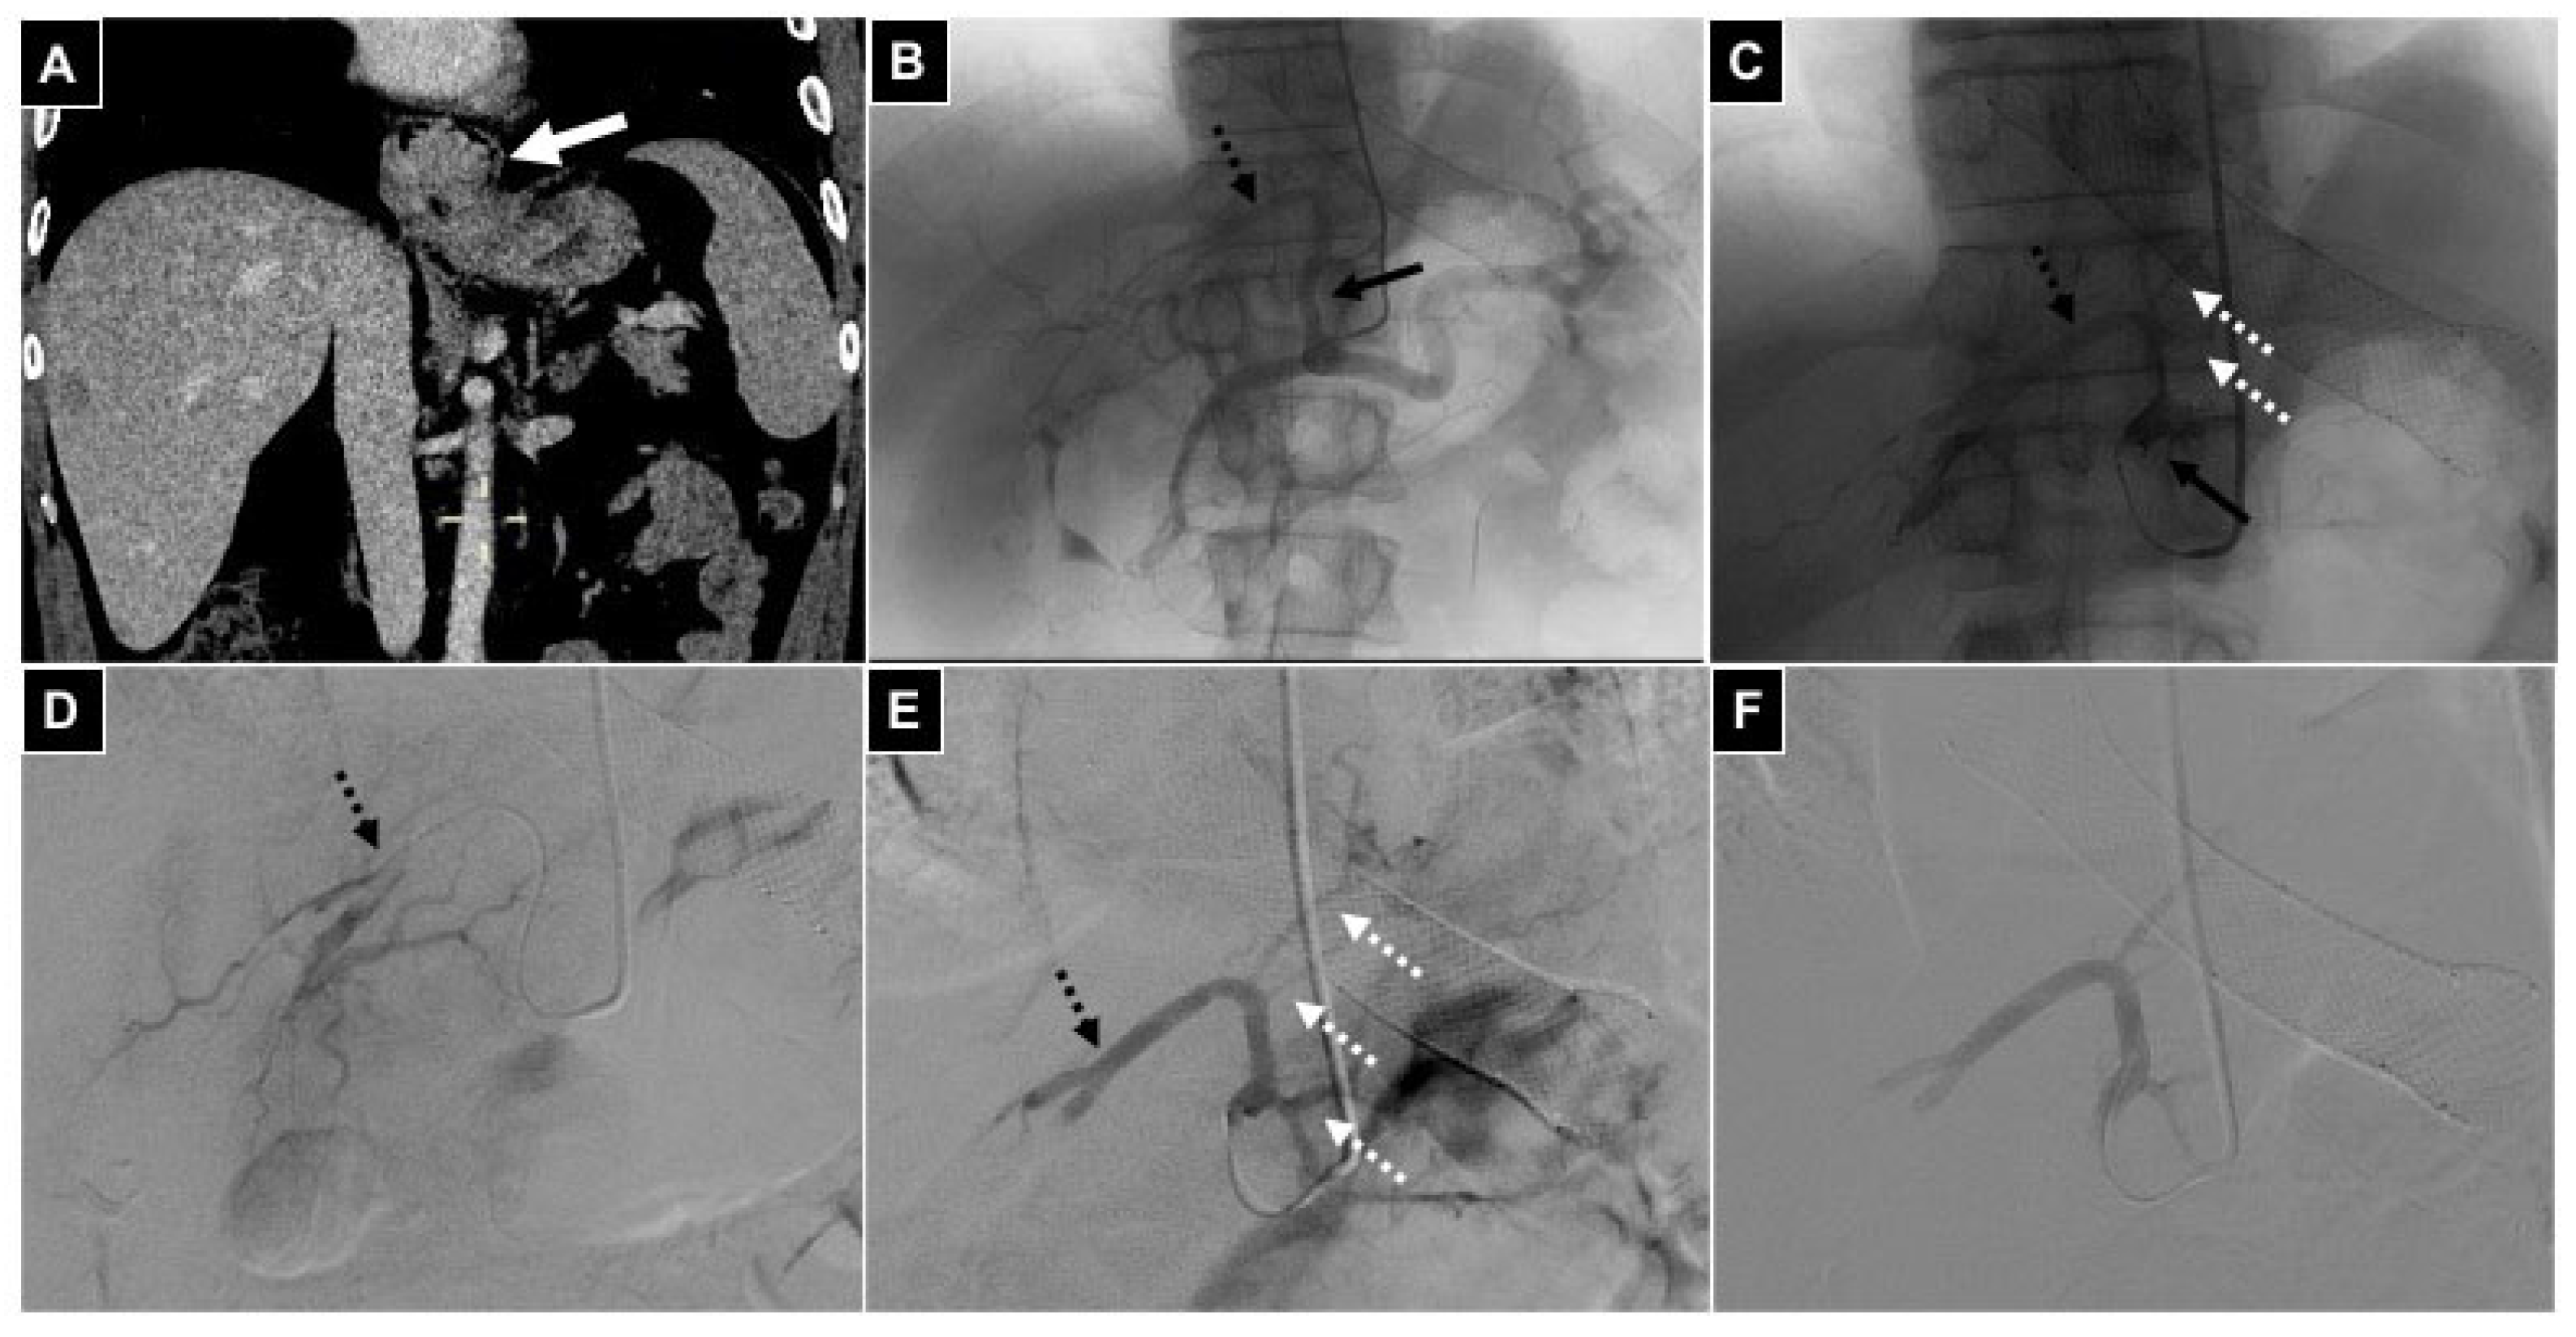

| 4 TARE | HCC | 2 Phrenic a. 2 Intrahepatic segmental a. | Intrahepatic a. | 99mTc MAA |